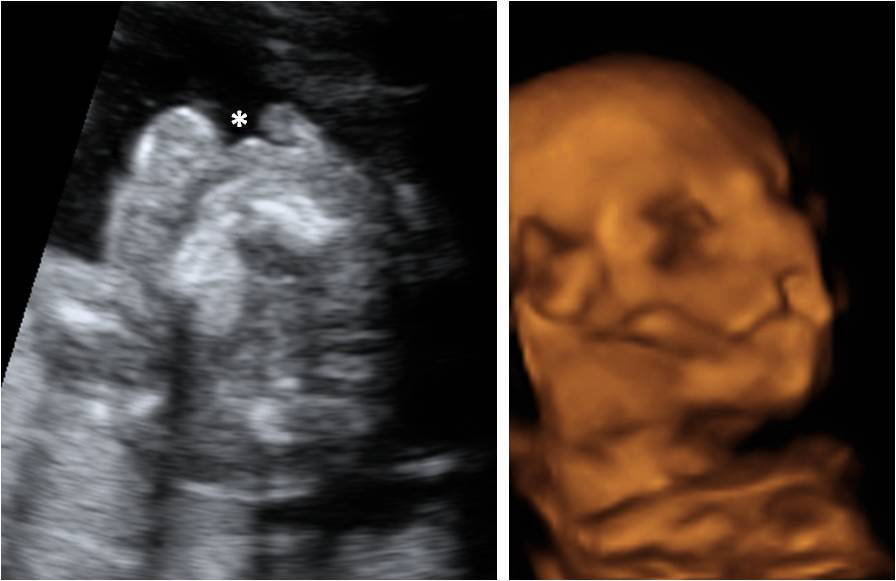

En la ecografía en 4D de un feto de 18 semanas de embarazo se ve la cara ya armonizada: las orejas y los ojos que en un principio estaban desplazados, ya se encuentran en su lugar, lo que le da una imagen mucho más "humana".

A esta edad temprana, apenas 20 semanas de gestación, las estructuras faciales básicas están prácticamente conformadas.